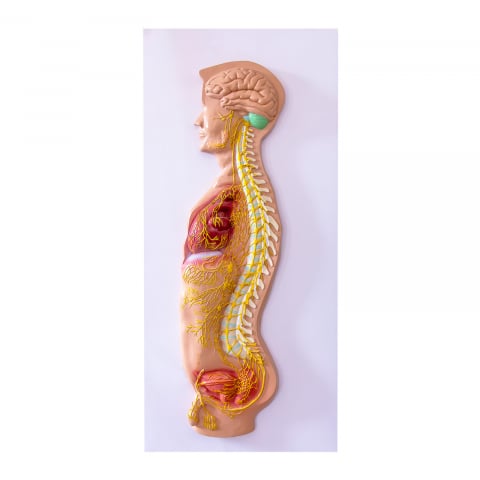

Modelul este conceput din material plastic PVC și este frumos colorat.

Acest model este conceput ca ajutor vizual pentru predarea cursurilor de anatomie umană și igienă. Este folosit pentru a demonstra structura dintelui, la studiul sistemului digestiv în gimnaziu, liceu și școli postliceale medicale.

Acest model are înălțimea de 23-26 cm, prezintă 3 rădăcini, o secțiune longitudinală prin care se poate observa structura interioara a dintelui, este conceput din material plastic PVC și este frumos colorat.